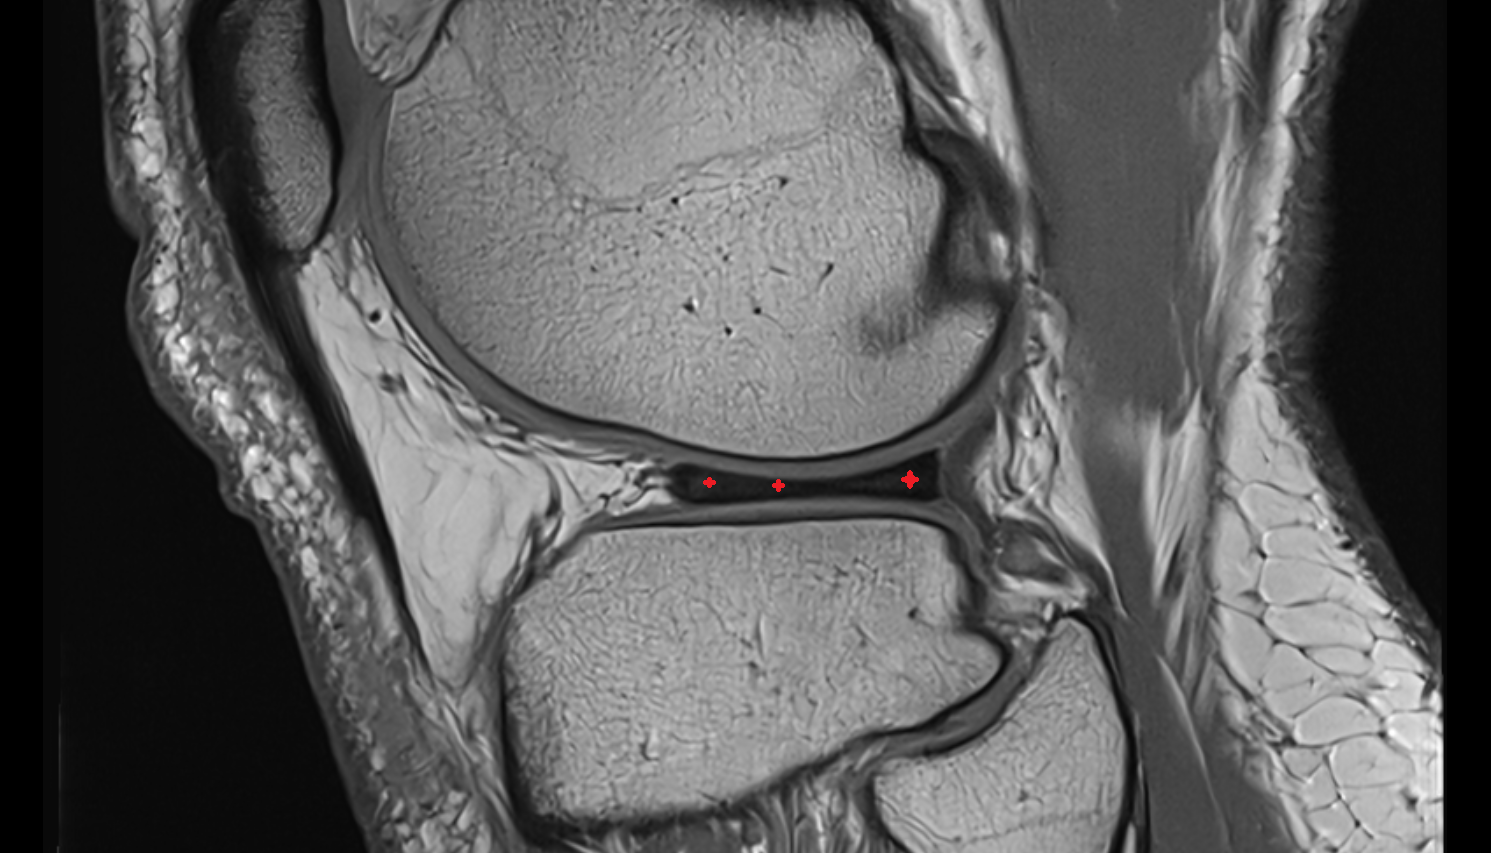

- Anterior cruciate ligament

- Posterior cruciate ligament

- Medial meniscus

- Lateral meniscus

- Knee Joint